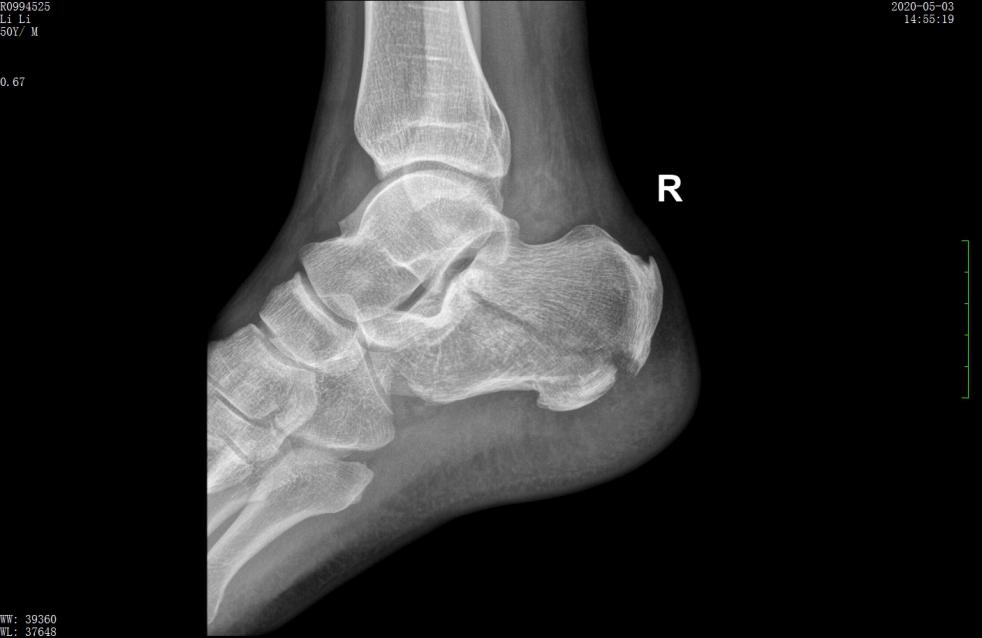

术前X线示跟骨高度丢失,关节面塌陷